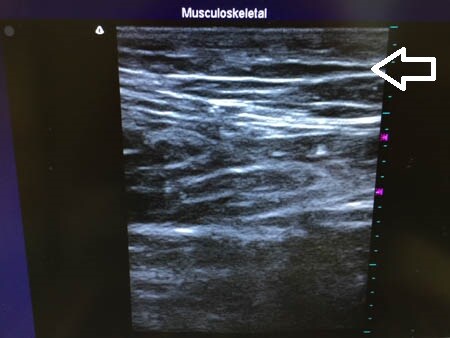

右太もも後面。